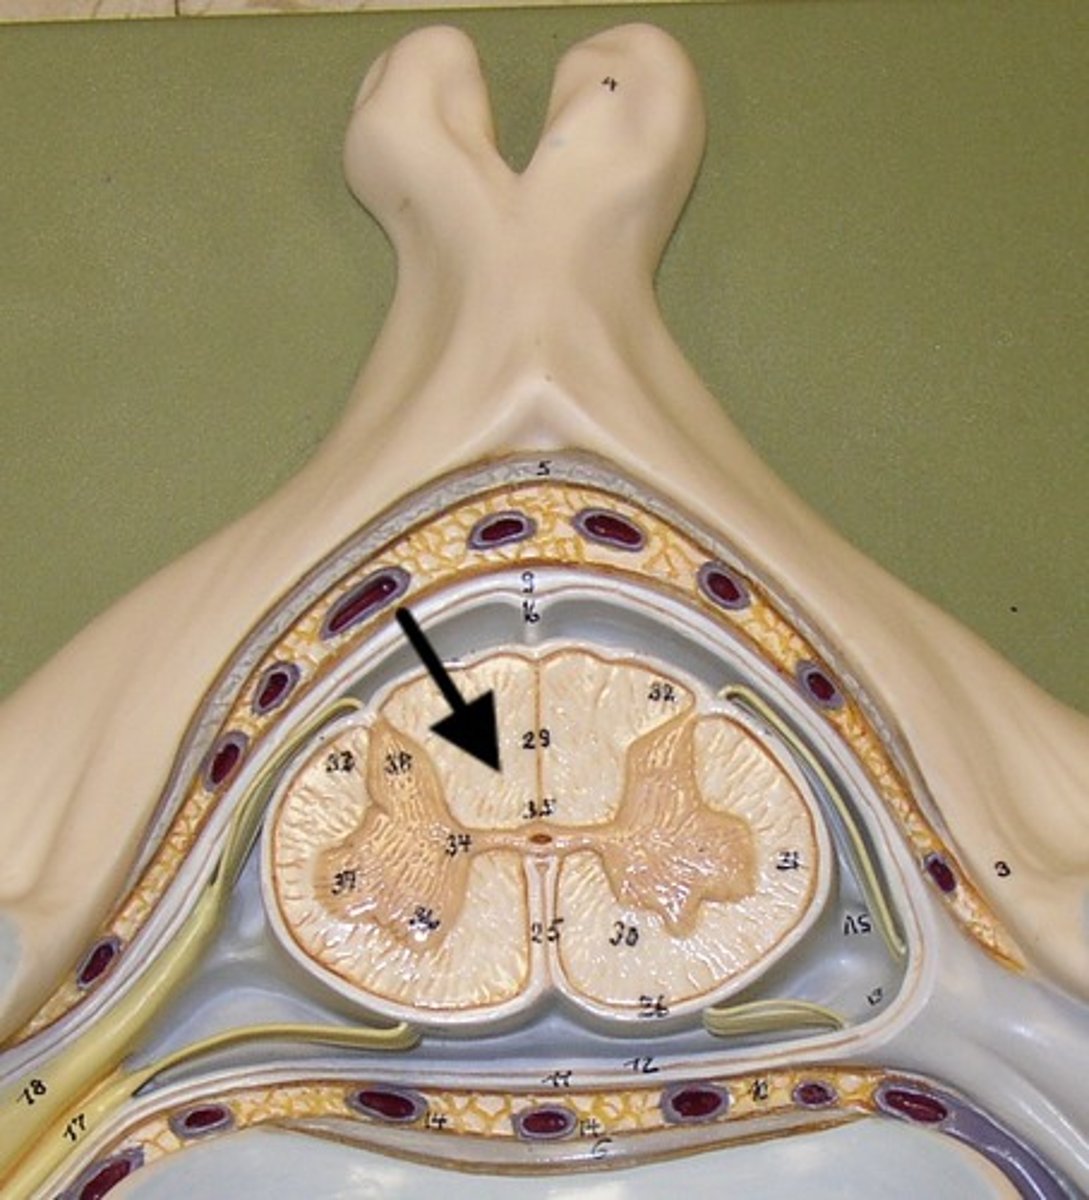

Spinal cord Anatomy (cross-sectional)

1)Internal butterfly shaped gray matter,

2)Exterior white matter,

3)Central canal filled with cerebrospinal fluid (CSF),

4)Cushioned & protected by meninges,

5)Pia mater,

6)Spinal nerves leave at the level of each vertenrae

Horns of Spinal Cord Anatomy

Dorsal Horns,

Ventral Horns,

Lateral Horns

Dorsal Horns

Lateral Horns

Ventral Horns

Interneurons

exterior white matter of the spinal cord

Ascending (sensory) and descending (motor) myelinated nerve tracts,

Posterior, anterior, lateral columns or funiculi

Posterior Columns

Anterior Columns

Lateral Columns/ funiculi

Central canal filled with what?

Central canal filled with cerebrospinal fluid (CSF)

Cushioned and protected by meninges

1) Cover the spinal cord

2) Dura mater, Arachnoid & Pia mater

dura mater of spinal cord

1) Separated from the periosteum by the epidermal space (fat, blood vessels)

2) Subdural space between dura and arachnoid mater

Dura Mater